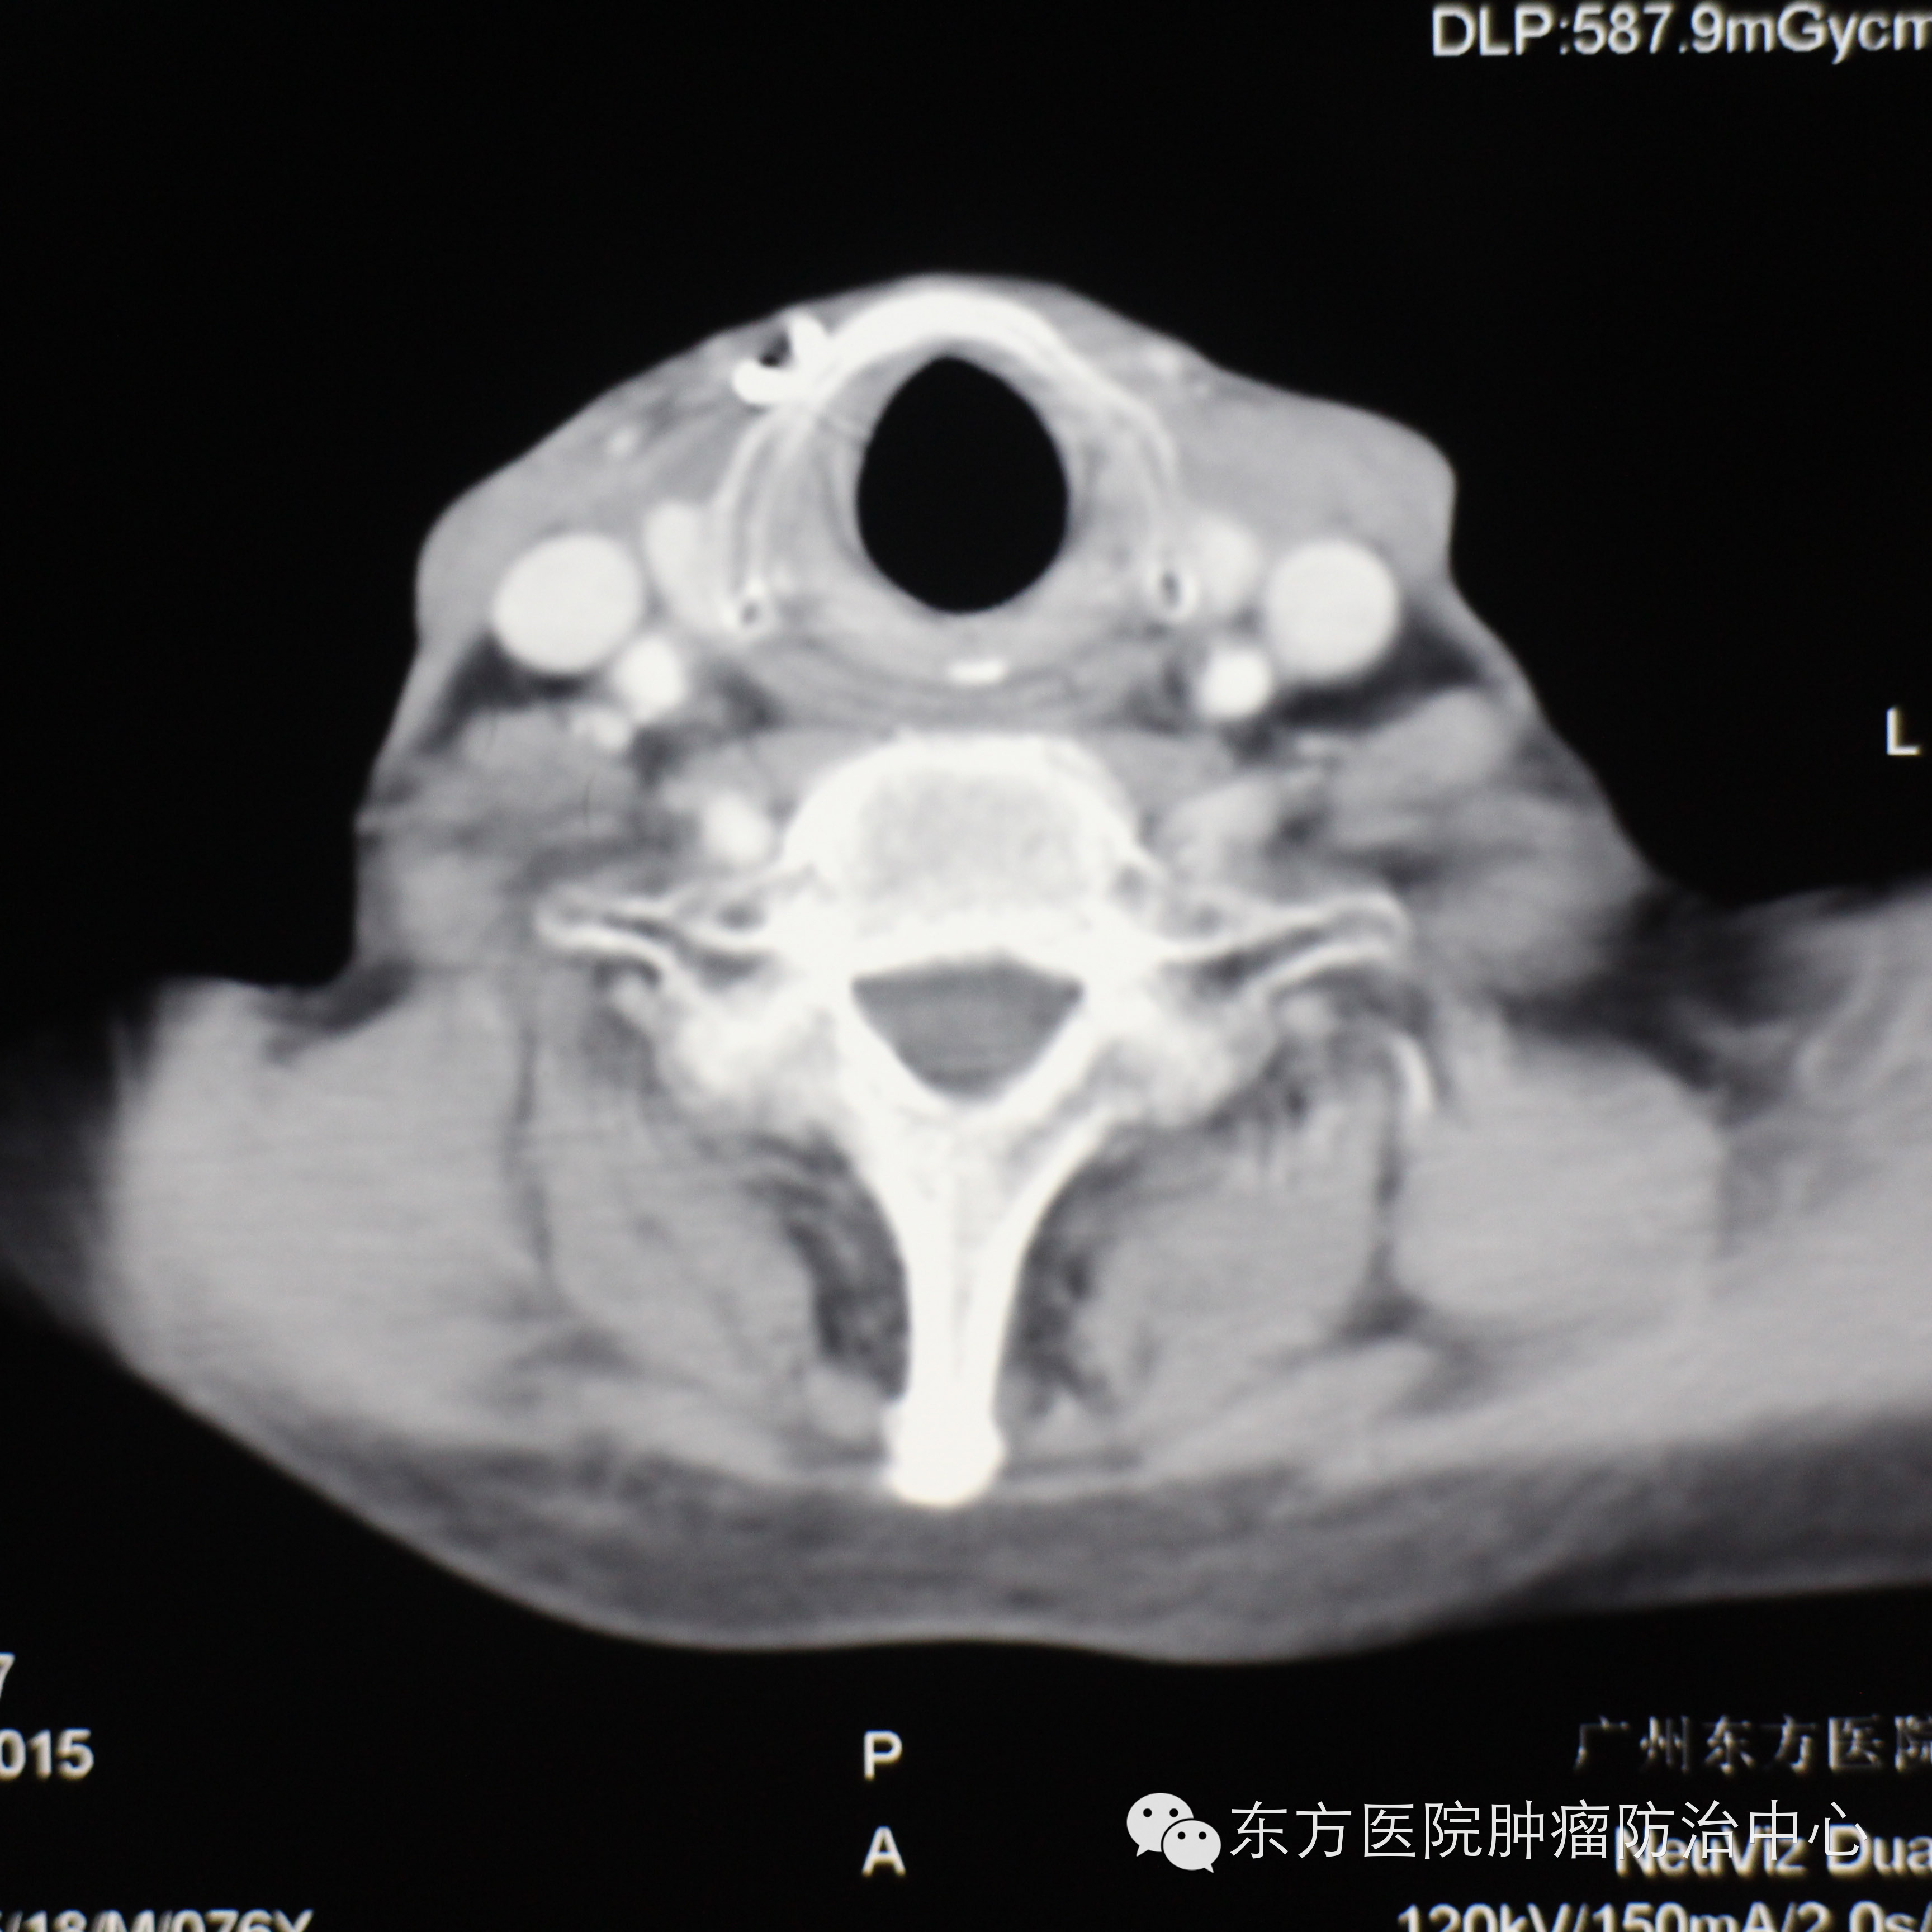

2009年张老先生在我国顶尖的肿瘤专科医院检查出喉部患高度恶性肿瘤并被下死亡书。命不该绝的他有幸认识广州东方医院肿瘤中心的姚波主任,为他的喉部恶性肿瘤进行治疗。八年后的今天,78岁的张老先生在儿子、女婿的陪同下回来复查,CT显示肿瘤已经完全消失,张老先生已经恢复了健康,跟常人无异。

CT显示肿瘤完全消失